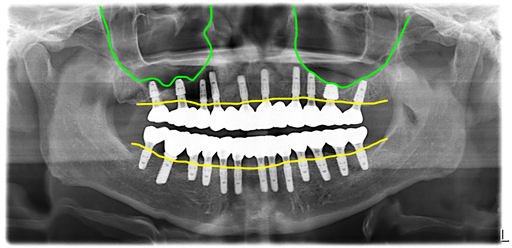

오늘 설명해 드릴 사례는 40대 남성 환자로 전체 치아에 충치가 모두 이환된 다발성 우식 환자의 전체임플란트입니다.

전체 치아가 모두 치아우식증, 즉 충치로 뿌리만 남은 치아도 많고 머리가 있다고 해도 곧 머리가 부러져 나갈 지경이었습니다.

콜라를 많이 드셔서 일까요? 이렇게 모든 치아가 다 썩어서 망가지기도 어렵지 않겠나 싶은데아무튼 임플란트 1개를 제외하고 모든 치아가 다 썩어서 망가져 있었어요.

그래서 결국 모든 치아를 제거하고 전체임플란트로 치료하기로 했고, 예전에 심은 임플란트는 이용해서 마무리하기로 했습니다.

리프팅한 뼈이식 조직도 잘 정착이 되었고 모든 임플란트가 문제없이 골융합이 이루어졌습니다.

잇몸이 좋지 않은 경우가 아닌 충치로 치아를 뽑게 된 경우라 잇몸뼈의 라인이 아주 좋습니다. 이렇게 잇몸뼈의 라인이 평평하면 관리에도 유리하고 심미적으로도 보기에 좋습니다.

전체 내원 4회 (수술, 실밥, 스캔, 세팅) 치료기간 6개월에 모든 치료를 완료하셨습니다. 상악 좌우 구치부에 뼈이식한 부분은 초기고정이 약해서 수술시에 잇몸 속에 임플란트를 넣어두었어요.